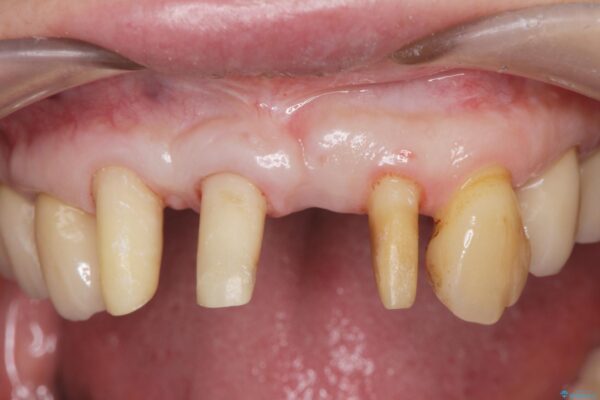

治療前

歯の総合的なマネージメントを行う包括的歯科治療の実践[ 歯周病・矯正・セラミック補綴 ] 治療前画像 歯の総合的なマネージメントを行う包括的歯科治療の実践[ 歯周病・矯正・セラミック補綴 ] 治療前画像 歯の総合的なマネージメントを行う包括的歯科治療の実践[ 歯周病・矯正・セラミック補綴 ] 治療前画像 歯の総合的なマネージメントを行う包括的歯科治療の実践[ 歯周病・矯正・セラミック補綴 ] 治療前画像 歯の総合的なマネージメントを行う包括的歯科治療の実践[ 歯周病・矯正・セラミック補綴 ] 治療前画像 歯の総合的なマネージメントを行う包括的歯科治療の実践[ 歯周病・矯正・セラミック補綴 ] 治療前画像 歯の総合的なマネージメントを行う包括的歯科治療の実践[ 歯周病・矯正・セラミック補綴 ] 治療前画像